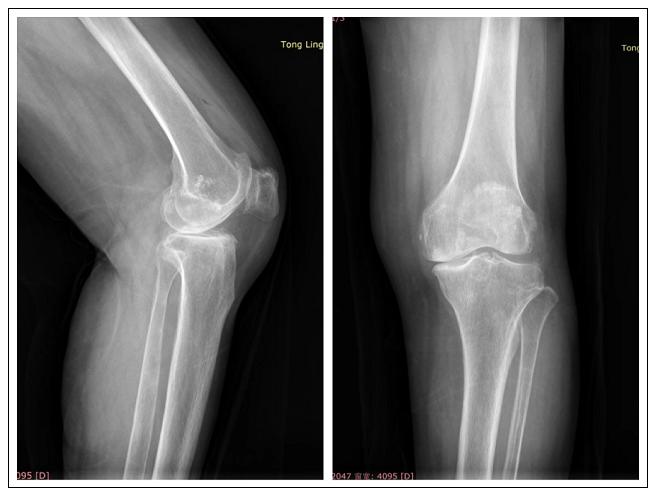

患者是名75岁女性,10年前出现左膝疼痛、行走困难,休息可缓解,现症状逐渐加重入院,诊断为:左膝内侧单间室骨关节炎。经过多项评估后,关节病区团队进行设计,为周某制定了个性化精准的手术方案,于10月20日为患者进行了左膝关节单髁置换术。术中仅置换膝关节内侧部分结构:股骨内髁、内侧半月板、胫骨平台内侧,保留了交叉韧带、髌骨及外侧结构的完整性。手术切口小、创伤小,技术细节要求较高、难度较大。术后第二天患者便可下地活动,做蹲起训练,现患者已康复出院。

单间室退变是膝关节骨性关节炎的最常见病理改变,膝关节单髁置换(Unicompartmental Knee Arthroplasty, UKA)就是针对单间室退变进行的精准化治疗。相对于传统膝关节置换,最大限度地保留了关节的正常部分,创伤更小、疗效更佳,患者的舒适度更高。